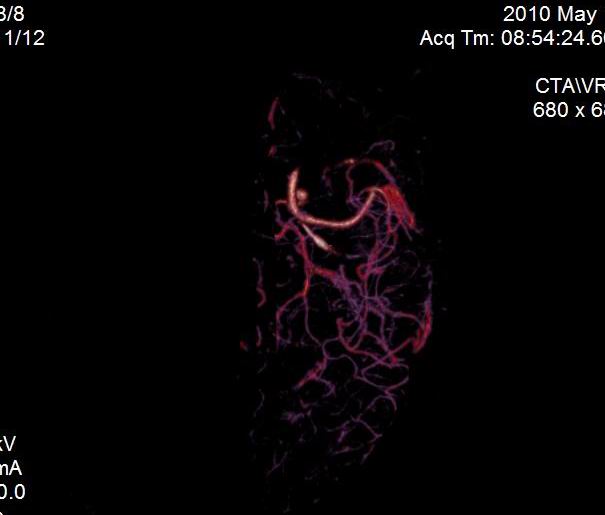

男.60岁,渐进性意识不清,ct检查双侧额颞顶部硬膜下血肿,开颅术后行脑血管cta,大脑中动脉起始部见一瘤状血管扩张。请各位老师留下宝贵意见

太常见了,报动脉瘤就可以

符合动脉瘤表现。

符合动脉瘤表现。

动脉瘤。

颅内动脉瘤。

后重建做得不是很好看,要将维蒂斯环充分显示,最好在增加一个mip。这样不好定位。

小动脉瘤

典型

符合动脉瘤的表现

动脉瘤

符合动脉瘤表现。

小动脉瘤

典型